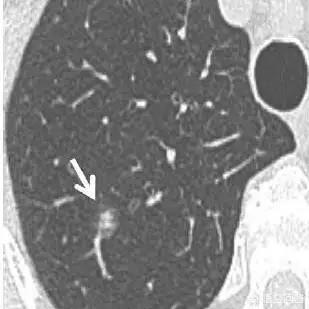

通常、異型腺腫性過形成の病変は5mm以内で、8mmを超えることは比較的まれである。下は8mm大の異型腺腫様過形成のCTと病理像である。

手術の機会に達していないと思われる、あるいは非定型腺腫様過形成の段階にある可能性のある地肌結節の場合。経過観察中に、すぐに手術が必要な状態とは??フィルム読者は、病変の前後を注意深く比較し、もし病変が見つかったら病変が以前の病変よりわずかに大きいか、あるいはわずかに密度が高いか、あるいは血管が病変の中に伸びているのが見つかる。例えば、下の写真は手術の時期だ。